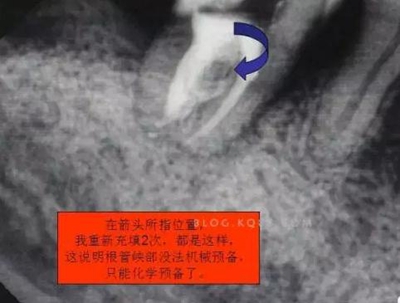

圖四

開髓完后,總覺得是不是牙體量去多了,拍片給人這種直觀感覺。

1.拍片基本可以確定遠中頰側根管是一個融合根管,也就是常見的C型根管,粗大的根管口是扁形,根管同樣呈扇貝型,根尖孔粗大。而且在根管中上段較粗大,插針拍片后遠中顯示根管有側穿的可能,但是通過內窺鏡顯示是沒有任何側穿點,也沒有滲血和患者有疼痛現(xiàn)象。這個病例告訴我們,有時候做根管治療,為了把根管做通和預備到位,必要的牙體組織去除是可以的,后期可以用冠修復來彌補,如果不去除,本病例的根管治療,根充時可能會面臨充填不嚴密,從而導致根管治療的失敗,這是不可取的。